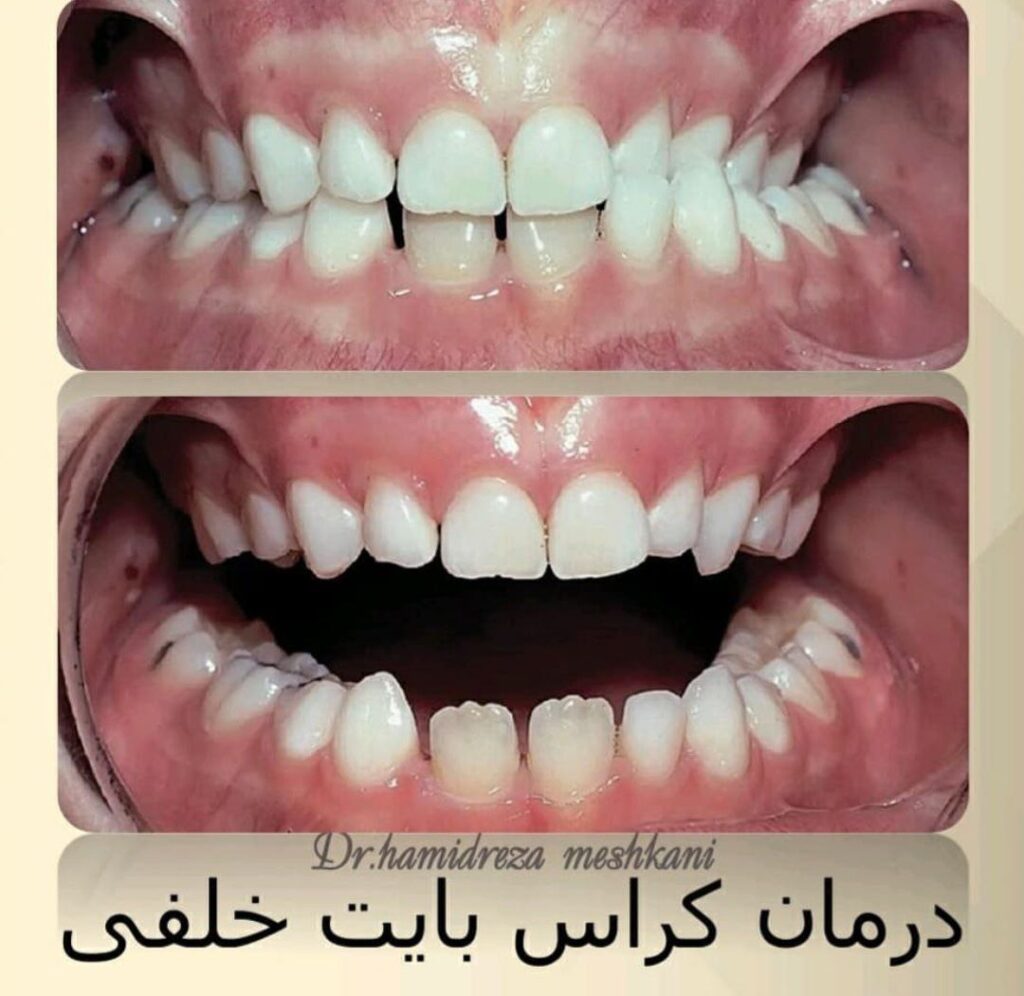

ارتودنسی در واقع یکی از شاخههای تخصصی دندانپزشکی است که برای زیباتر شدن صورت و دندانها و بهبود عملکرد آنها مورد استفاده قرار میگیرد. کجی دندانها، اوربایت و آندربایت (جلوتر بودن بیش از اندازه دندانهای بالا یا پایین)، کراس بایت، شلوغی دندانها و اختلالهای مربوط به فک از مشکلاتی است که توسط متخصصان ارتودنسی درمان میشود. در مواردی متخصص اطفال دندانپزشکی ویا دندانپزشک عمومی نیز اقدامات درمانی ارتودنسی رانیز انجام میدهند.